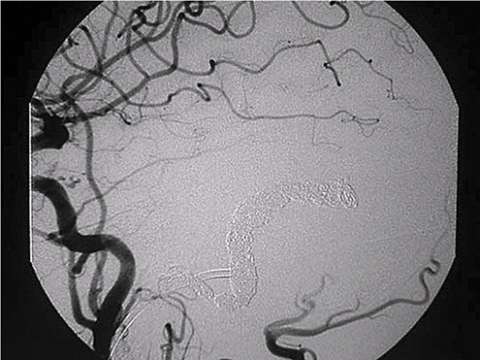

First step of the treatment is to obtain an entire picture of a DAVF and characterize it. Cerebral angiography (dye injection into brain arteries through a plastic tube) is the gold-standard and the most accurate way to do so. Based on the finding of cerebral angiography and the symptoms, the following options are offered:

- Endovascular embolization

One of the most worrisome finding is so called "cortical venous reflux". This is the sign that blood flow return to the brain is compromised and associated with high risk of brain hemorrhage. Regardless of the symptoms, DAVF's with cortical venous reflux should be treated as soon as practical by either endovascular embolization or open surgery. Recently, most DAVF's can be treated by endovascular embolization.